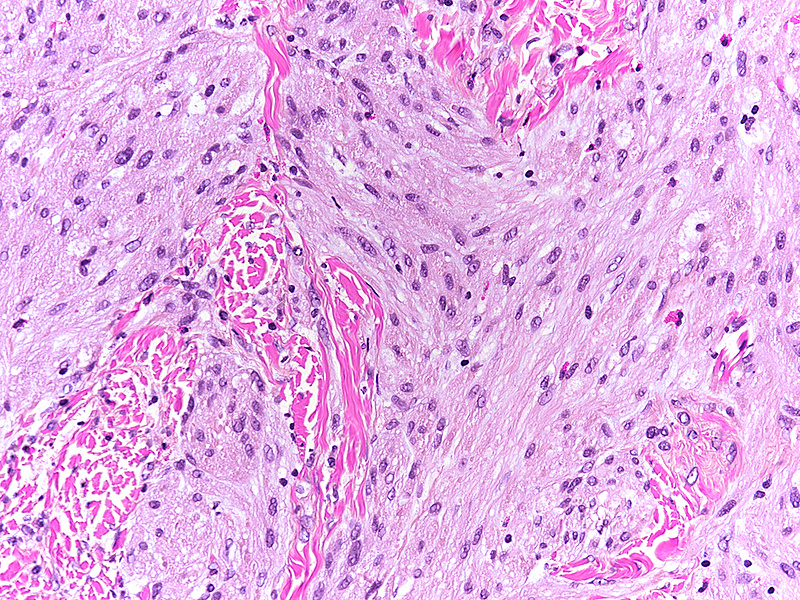

Histologically, we saw a submucosal proliferation of solid nests and ribbons of round to polyhedral cells, measuring approximately 6 mm in largest diameter (Panels A-B). The neoplastic cells generally contained small, uniform nuclei with inconspicuous nucleoli and abundant granular eosinophilic cytoplasm. They were separated by fibrous septa, which contained few inflammatory cells, mostly lymphocytes and few eosinophils (Panel C). In some areas, the neoplastic cells demonstrated cell spindling, still keeping the cytoplasmic features described above (Panel D). The lesion was ill-defined at the base, showing an infiltrative pattern into the surrounding adipose tissue within the submucosal layer (Panels E-F). The neoplastic cells were positive for PAS and strongly immunoreactive for S100-protein (Panels G-H), yet negative for keratin, CD117, DOG-1, and muscle markers, prompting final diagnosis of colonic granular cell tumour.

Granular cell tumors are common lesions in subcutaneous tissue. Gastrointestinal pathologists may encounter this form of peripheral nerve sheath tumour mainly in the oesophagus. In the colorectum, granular cell tumours prevail on the right side (coecum, around the ileocoecal valve, and within the ascending colon). On low power they are either infiltrative or well-defined, involving either the mucosa, submucosa (most common), or both. The cells are characteristically positive for PAS and S100-protein, but may also show positivity for SOX-10, NSE, and synaptophysin.